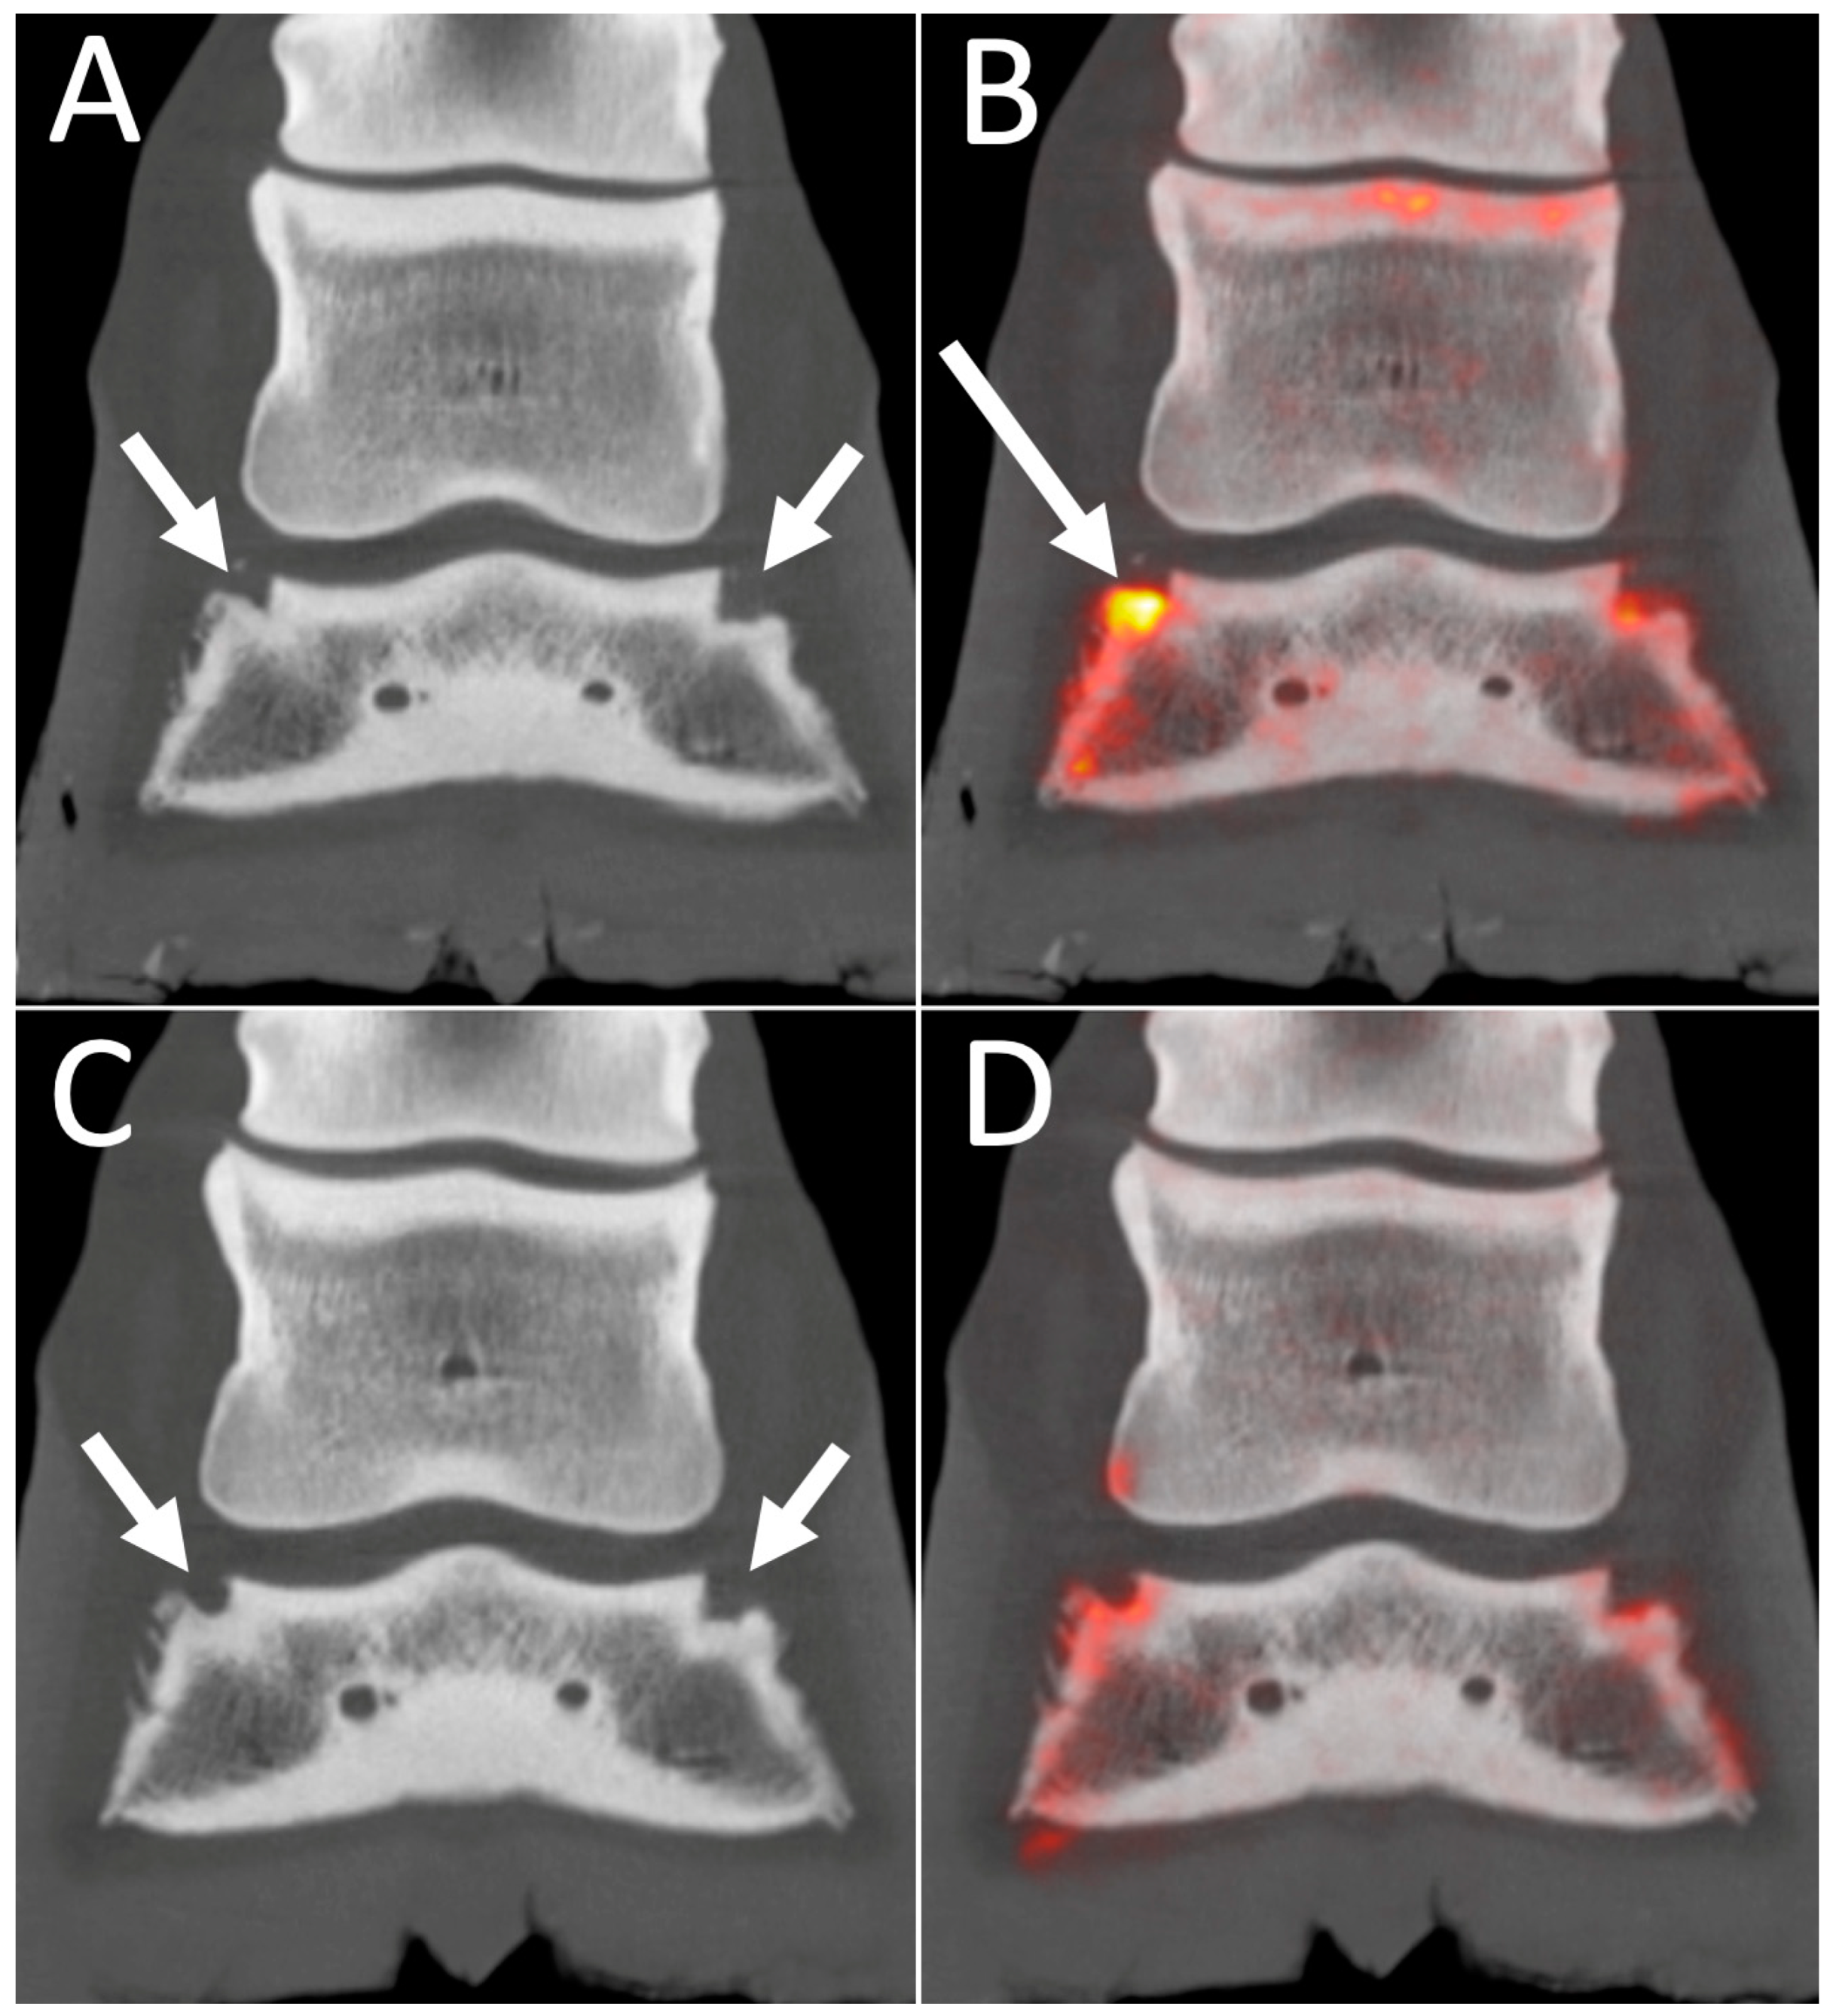

4.2. 18F-NaF PET Combined with CT or MRI for Optimal Bone Imaging

4.4. PET for Longitudinal Monitoring of Lesions

- Espinosa-Mur, P.; Spriet, M.; Manso-Diaz, G.; Arndt, S.; Perez-Nogues, M.; Roman, J.L.; Garcia-Mata, R.; Katzman, S.A.; Galuppo, L.D. 18F-sodium fluoride positron emission tomography provides pertinent additional information to computed tomography for assessment and management of tarsal pain in horses. J. Am. Vet. Med. Assoc. 2023, 261, 1638–1645. [Google Scholar] [CrossRef]